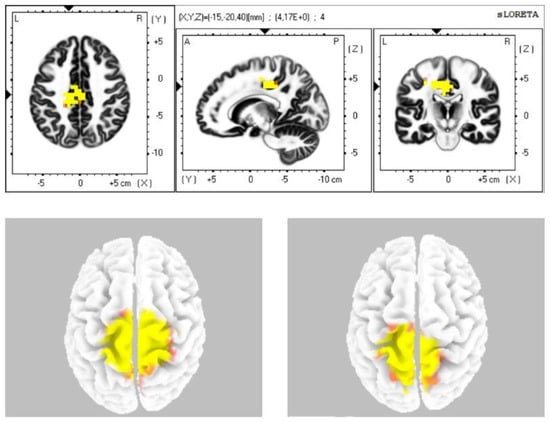

| Alpha-1 | 4, 3, 24 |

| Alpha-2 | 6, 4, 3, 24 |

| Beta-1 | 6, 4, 3 |

| Beta-2 | 6, 4 |